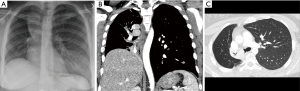

Chest computed tomography (CT) is a more sensitive study for evaluation of the airway lumen (Figure 3). Not only can a chest CT show endoluminal masses or extrinsic airway compression, but it may also reveal other signs of CAO including atelectasis, post-obstructive pneumonia, and dynamic airway collapse (2,21). Multi-detector CTs provide three-dimensional information to better characterize luminal involvement of lesions, more accurately measure their size, and help determine the patency of airways distal to the obstruction. CT imaging, particularly with contrast, is also crucial for delineating the relationship of airway tumors and adjacent vasculature. The information gained from CT imaging is incredibly valuable for developing the treatment approach prior to bronchoscopy, a procedure which is frequently necessary in the management of CAO and acts as both a diagnostic and therapeutic modality (2,24). It is important to note that mucus plugging and blood in association with a narrowed airway may lead to over-estimation of the length and degree of stenosis on chest CT, so lack of an obvious patent distal airway on imaging should not in itself prohibit performance of a bronchoscopy (19). Dynamic CT, an imaging method in which images are captured at the end of inspiration and during breathing, can evaluate for dynamic forms of CAO. These include tracheobronchomalacia and excessive dynamic airway collapse, conditions which may occur in conjunction with or independently from malignant CAO (21).

Figure 3 Chest X-ray (A), coronal (B) and axial chest CT (C) images from the same patient illustrating the additional detail gained with chest CT. CT, computed tomography.